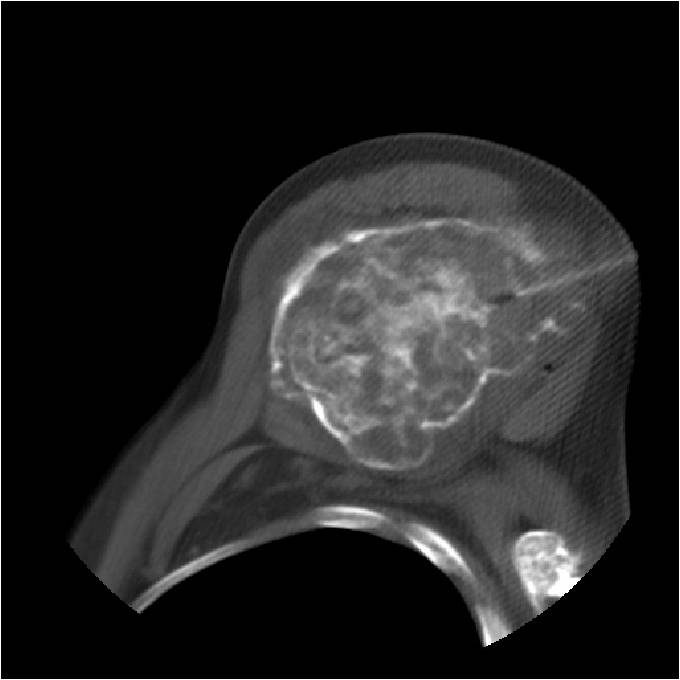

Ring and Arc Calcifications, Minimal Endosteal Scalloping, Cortex Intact, No Soft Tissue Component, No Periosteal Reaction

Minimal Endosteal Scalloping is Acceptable

Metaphyseal Tumor, Heavy Calcifications, Ring and Arc Pattern of Calcifications, Minimal Endosteal Scalloping, No Cortical Destruction, No Periosteal Reaction, No Cortical Destruction, No Soft Tissue Component

Metaphyseal Tumor, Heavy Calcifications, Ring and Arc Pattern of Calcifications, Minimal Endosteal Scalloping, No Cortical Destruction, No Periosteal Reaction, No Soft Tissue Component